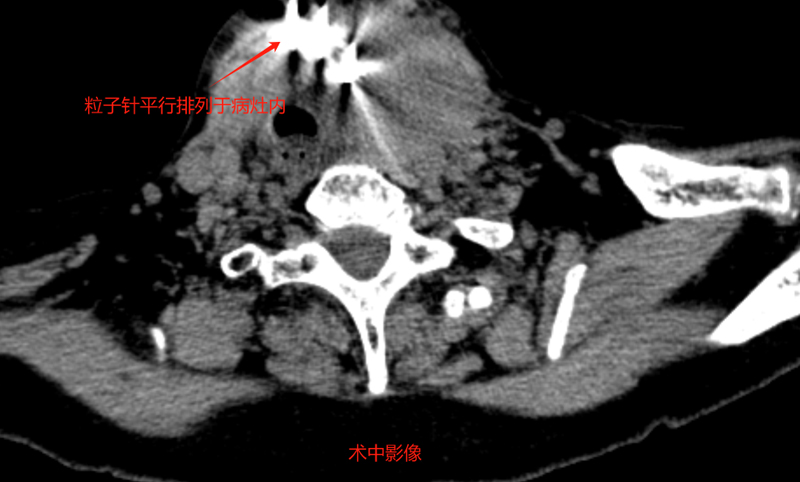

经过和患者家属的有效沟通,介入科团队为苑大娘补充了相关的检查,确定了治疗方案,于9月份在我院行“组织间粒子植入术”。由于复发病灶紧邻气管,且包绕了很多重要血管,无疑加大了操作难度。刘冰主任凭借多年的丰富经验,精细操作,将粒子精确植入到病灶内部,实现“精准爆破”。植入后患者无明显不适,很快顺利出院。